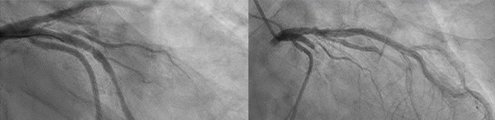

AccuFFRangio, 새로운 영상 기반 관상동맥

생리학적 검사법의 효용성

구본권/서울의대